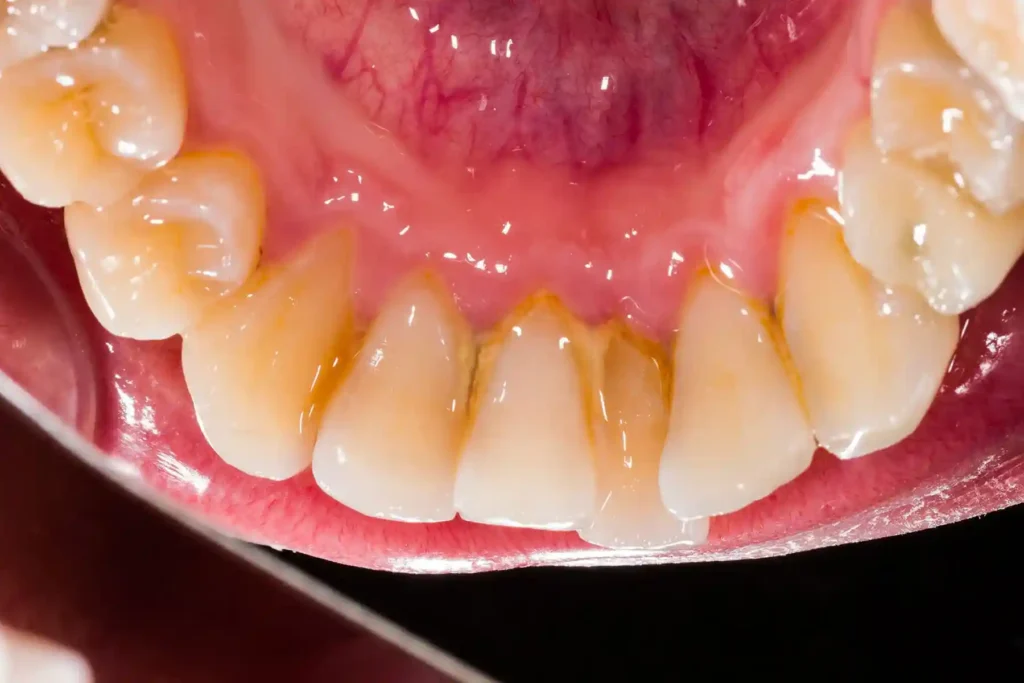

جرم دندان چیست و چگونه تشکیل میشود؟

جرم دندان (Calculus) در واقع پلاک میکروبی سختشده است که در اثر تجمع باکتریها و مواد معدنی بزاق روی دندان تشکیل میشود.

پلاک نرم → عدم مسواک مناسب → تجمع باکتری → رسوب مواد معدنی → تشکیل جرم سخت

جرم به مسواک عادی پاسخ نمیدهد و فقط با ابزار تخصصی دندانپزشکی برداشته میشود.

چه علائمی نشان میدهد به جرمگیری نیاز دارید؟

- تغییر رنگ زرد یا قهوهای کنار لثه

- احساس زبری روی دندانها